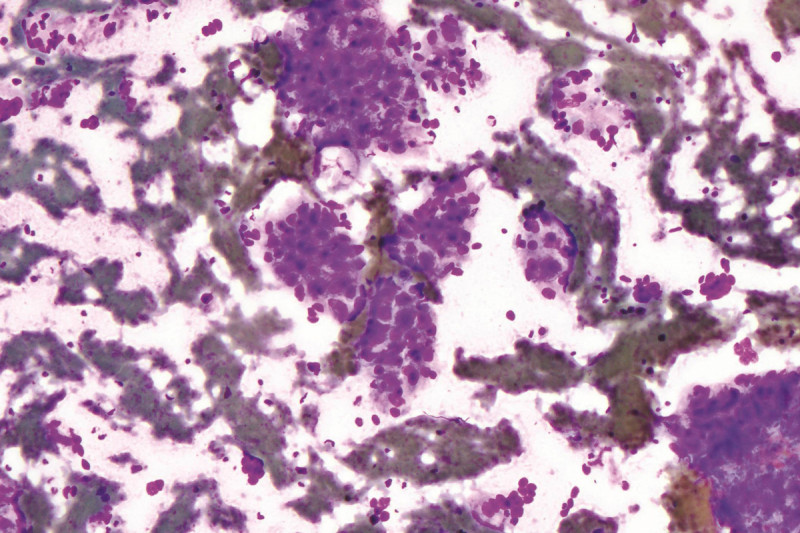

We use state-of-the-art technologies including telecytology, a process in which tissue specimen slides prepared in the IR procedure suite are placed in a specialized microscope, scanned into digital images, and transmitted to the Department of Pathology at MSK’s Manhattan location via a secure intranet connection. This approach increases diagnostic accuracy without the need for cytology personnel to be physically present, radically changing the way we provide biopsy services on an outpatient basis. Real-time feedback happens during the procedure while the patient is still on the table. The diagnostic accuracy rate is approximately 98% which is similar to that seen when biopsies are performed on site with conventional microscopes.